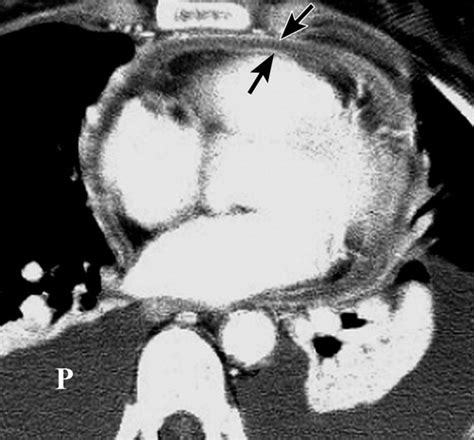

May 30, 2018 · scanner et imagerie par résonance magnétique (irm) ils permettent d'observer l'épaississement du péricarde, mais également la gêne du travail des ventricules dans le cas d'une péricardite constrictive.

May 30, 2018 · scanner et imagerie par résonance magnétique (irm) ils permettent d'observer l'épaississement du péricarde, mais également la gêne du travail des ventricules dans le cas d'une péricardite constrictive. Le scanner thoracique et l'irm cardiaque sont parfois utiles en deuxième intention lorsque le patient n'est pas échogène ou en présence d'une péricardite néoplasique ou d'un épanchement péricardique cloisonné. Elle peut s'accompagner ou non d'un épanchement péricardique et en cas de fibrose et calcifications (avec alors épaississement du péricarde) évoluer vers une péricardite constrictive qui gêne le. Troubles de la repolarisation diffus concordants dans toutes les dérivations ; L'irm a l'avantage de visualiser la cavité péricardique sans injection de produit de contraste ni irradiation. Une tachycardie sinusale et des troubles du rythme des oreillettes sont fréquents. Le scanner thoracique et l'irm cardiaque sont parfois utiles en deuxième intention lorsque le patient n'est pas échogène ou en présence d'une péricardite néoplasique ou d'un épanchement péricardique cloisonné. Le traitement de la péricardite. May 10, 2016 · l'échographie apprécie l'importance de l'épanchement mais chez certains patients, l'échographie est négative. Les radiographies simples telles que le scanner (thorax, abdomen) ou l'échographie (cœur, abdomen, testicule) permettent de confirmer l'épanchement et d'en préciser l'étendue et les conséquences. L'irm a l'avantage de visualiser la cavité péricardique sans injection de produit de contraste ni irradiation. L'analyse du liquide est souvent nécessaire dans les épanchements pleuraux et articulaires ainsi que dans l'ascite. Jun 11, 2019 · dans ces cas, le scanner thoracique ou l'irm peuvent être utiles ;